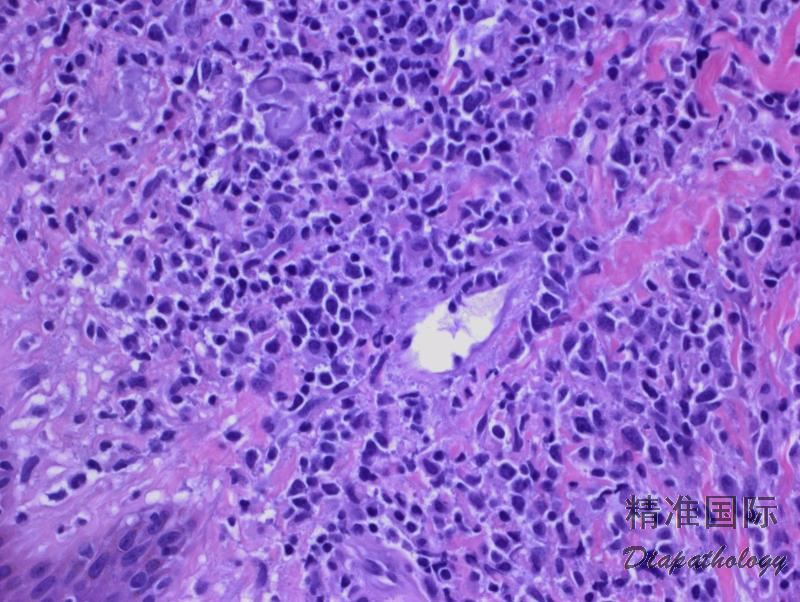

肿瘤细胞大小因病例而异,可以是小型细胞,也可以是中等或大细胞或混合大小细胞。小细胞核轮廓不规则,染色质密集、核仁不明显,胞质淡染,少量至中等。中等大小细胞核呈圆形或有不规则核皱褶,染色质呈颗粒状,核仁小,胞质含量中等,淡染至透明。大细胞表现为核圆形,空泡状或颗粒状染色质,有明显核仁。